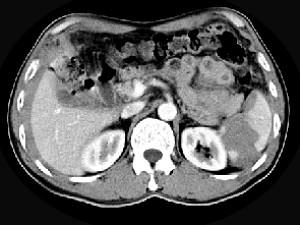

问题 男,55岁,左上中腹部突发性疼痛,CT扫描如图,最可能的诊断是 ( )

选项 A、脾脓肿 B、脾转移瘤 C、脾淋巴瘤 D、脾血管瘤 E、脾肿瘤破裂出血

答案 E